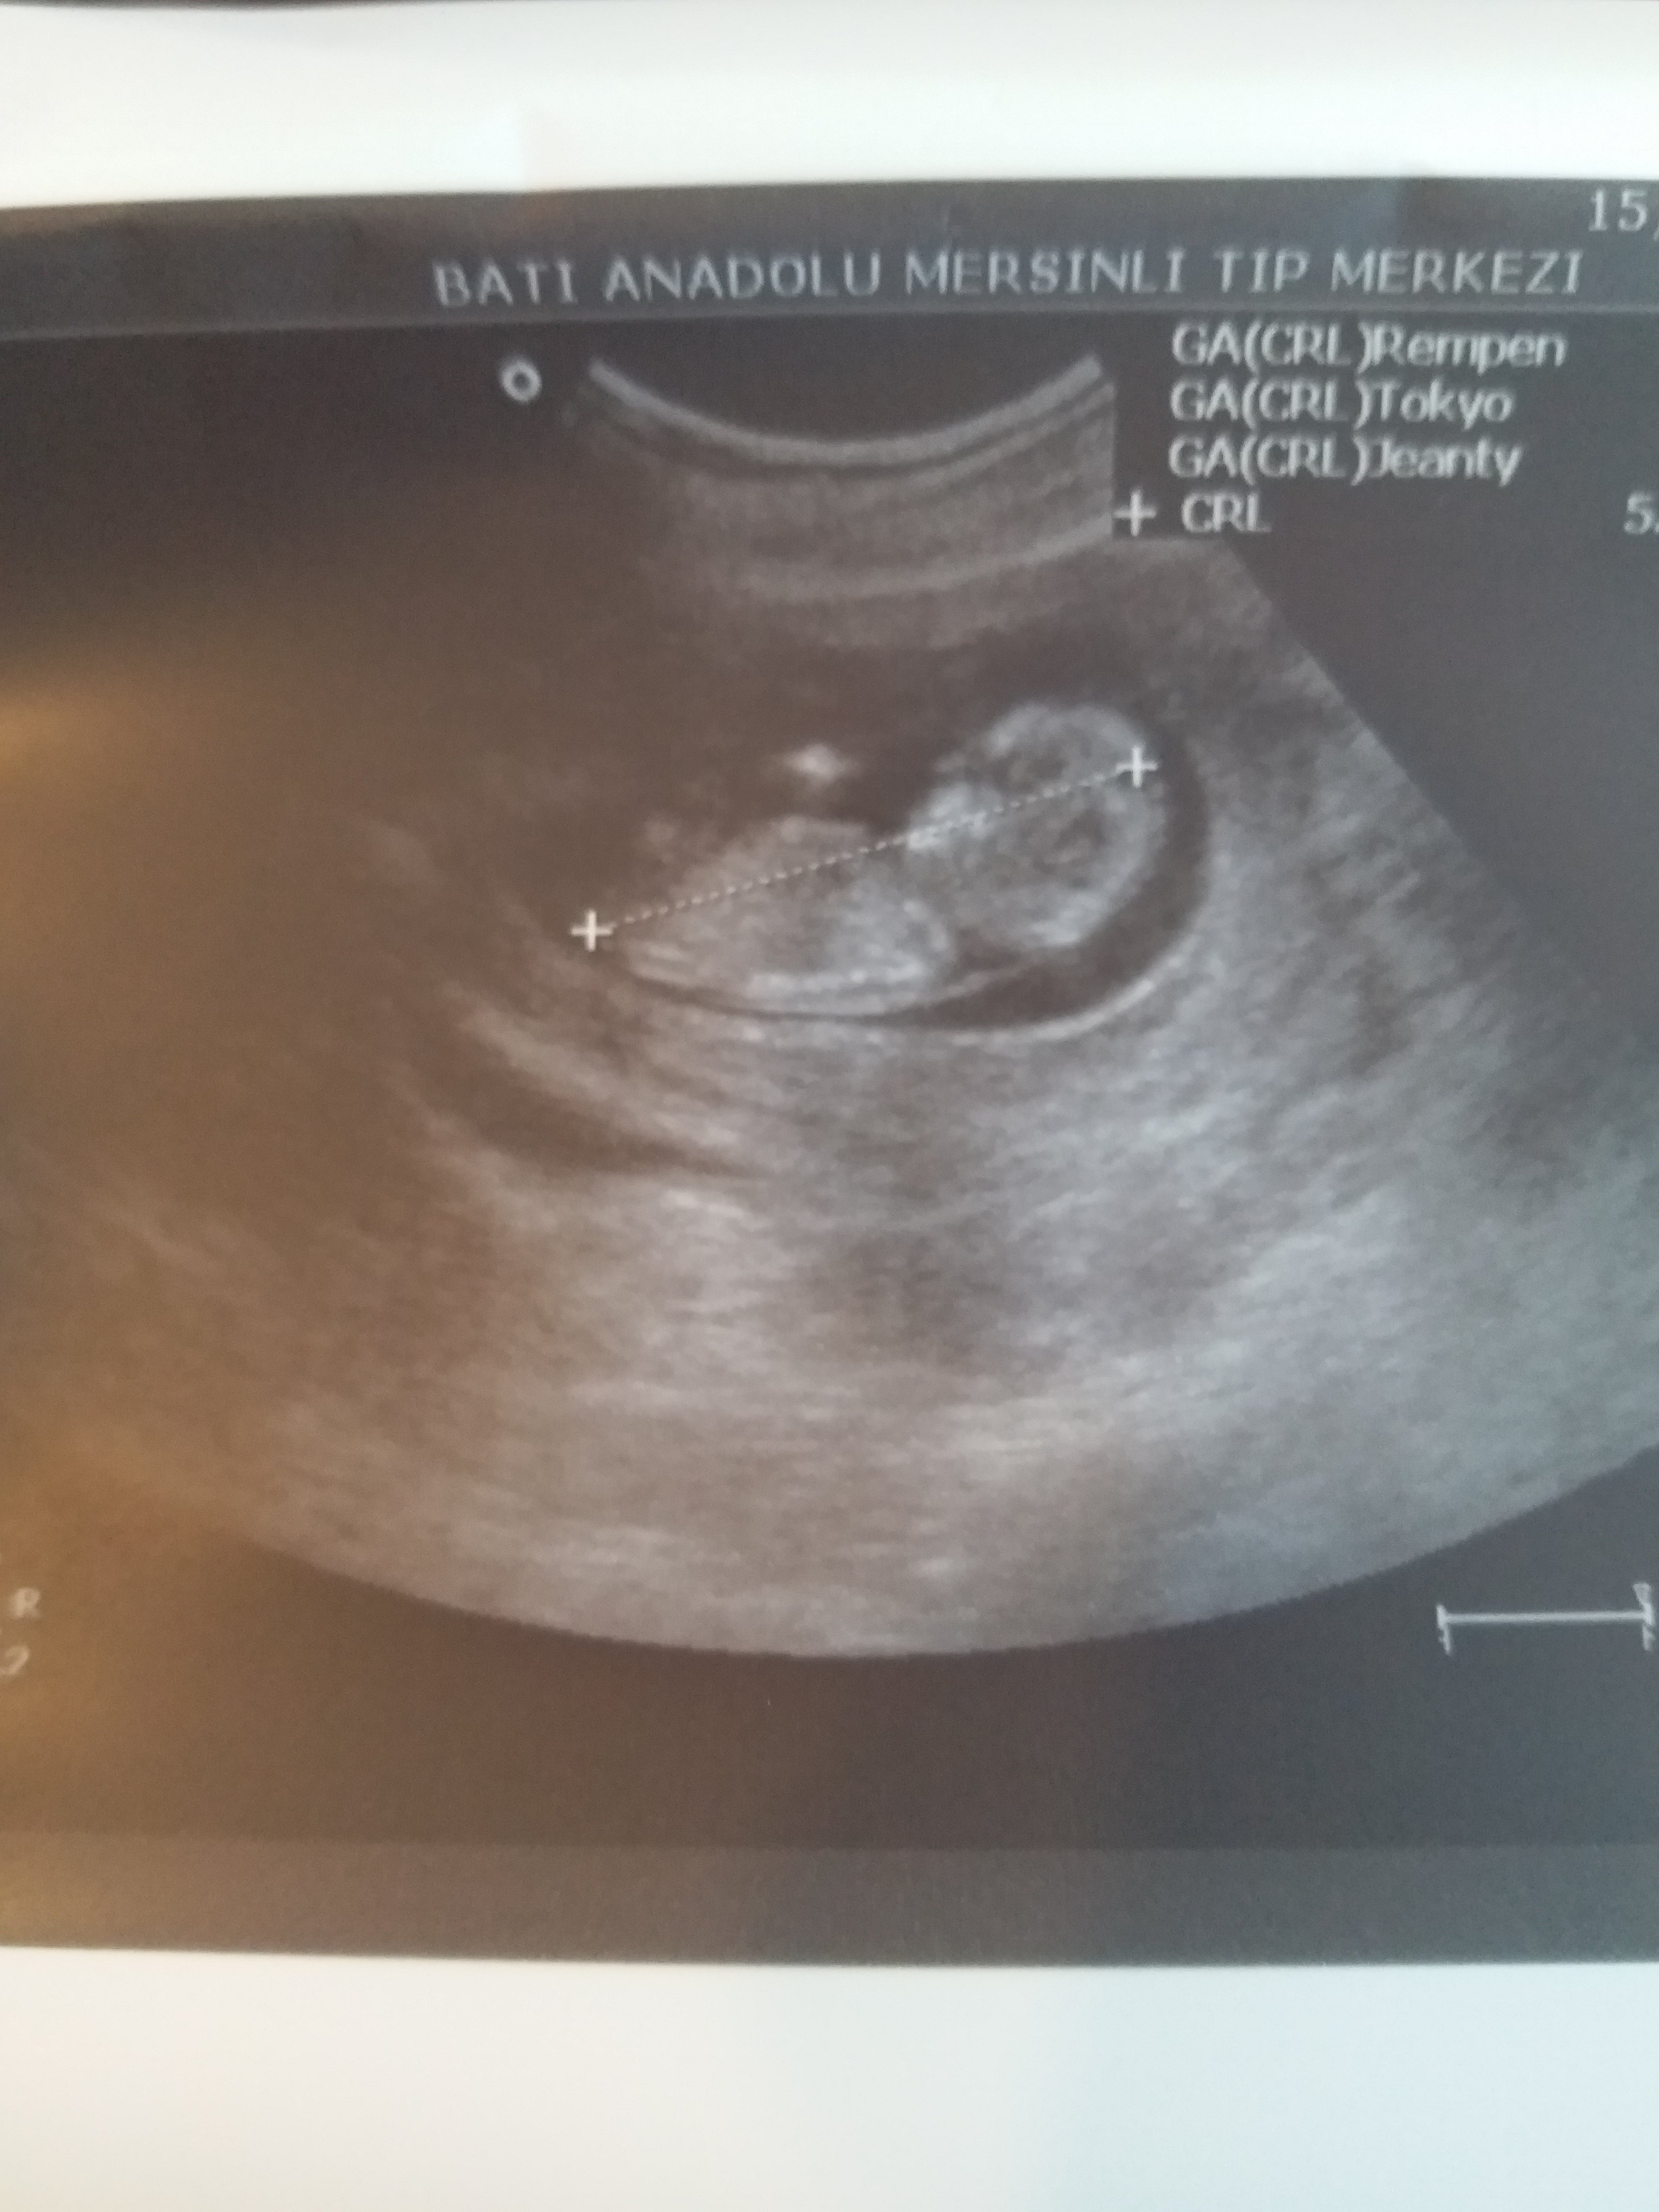

Daha önce de belirtildiği gibi, hem erkek hem de kız fetusların gelişme aşamalarında genital bir tüberkül vardır. Bu genital tüberkül bir nub olarak adlandırılır.Nub Teorisini kullanarak bebeğinizin cinsiyetini belirlemek, büyük oranda ultrason resmine bağlıdır. Bu, nub resminin sonucu belirlemeniz için mükemmel olması gerektiği anlamına gelir.

Resimde gördüğünüz gibi üst taraftaki çıkıntı paralel ise bebek kız, 30° lik açıyla yukarı bakıyorsa bebek erkektir.

Gebeliğin 9. haftası fetusun bacaklarının arasın da küçük bir çıkıntı görülür. Gebeliğin 12. ve 14 haftası bu topak çıkıntı nın açısı değerlendirilerek , cinsiyet tahmini yapılır. Çıkıntı kızlar da 30 derecenin altın da ve düzdür erkekler de ise 30 derecelik açıdan büyüktür.

Nub teorisin de cinsiyet belirleyen uzmanlar 12- 14 . haftalar da genital tüberkül görünürlüğü kontrol edecektir.Bebeğin pozisyonu , kese içinde amniyotik sıvı miktarı, karın duvarı, tarama kalitesi veya çözünürlük kalınlığı etkilenebilir. Cinsiyet belirlemek için, Cinsiyet Uzmanları aşağıdaki ölçütleri kullanmaktadır.

Görünürlük , omurga ile ilgili genital tüberkül açısı , Gölgeler ve erkek belirteçler ve topak çevreleyen ucu , Gebelik yaşına göre uzunluğu da dahil olmak üzere, şekil.. Nub teorisi ile cinsiyet belirleme de tarama omurga görüntüleme ve buna özü ilişkisini sağlamak için, profil görünümünde olmalıdır.